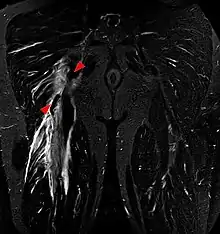

Imaging the hamstring muscles is usually performed with an ultrasound and/or MRI.[7] The biceps femoris is most commonly injured, followed by semitendinosus. Semimembranosus injury is rare. Imaging is useful in differentiating the grade of strain, especially if the muscle is completely torn.[8] In this setting, the level and degree of retraction can be determined, serving as a useful roadmap prior to any surgery. Those with a hamstring strain of greater than 60mm in length have a greater risk of recurrence.[9]